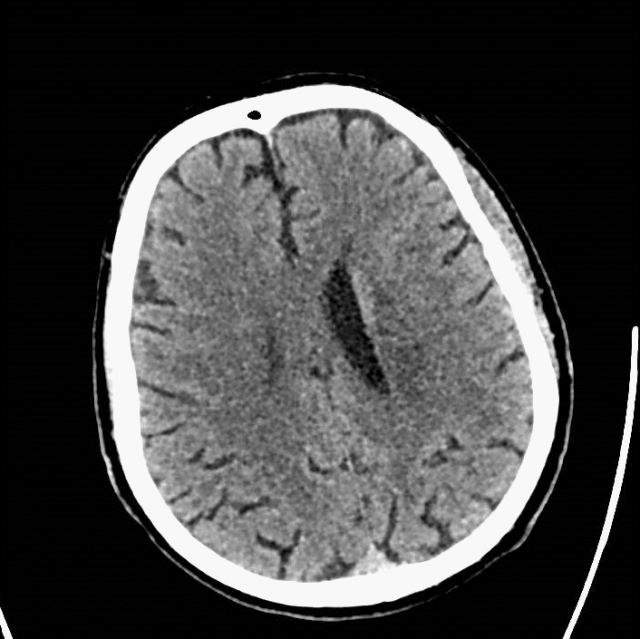

术前评估

颅脑CT平扫:左侧基底节、放射冠及侧脑室后角可见散在片状低密度灶。